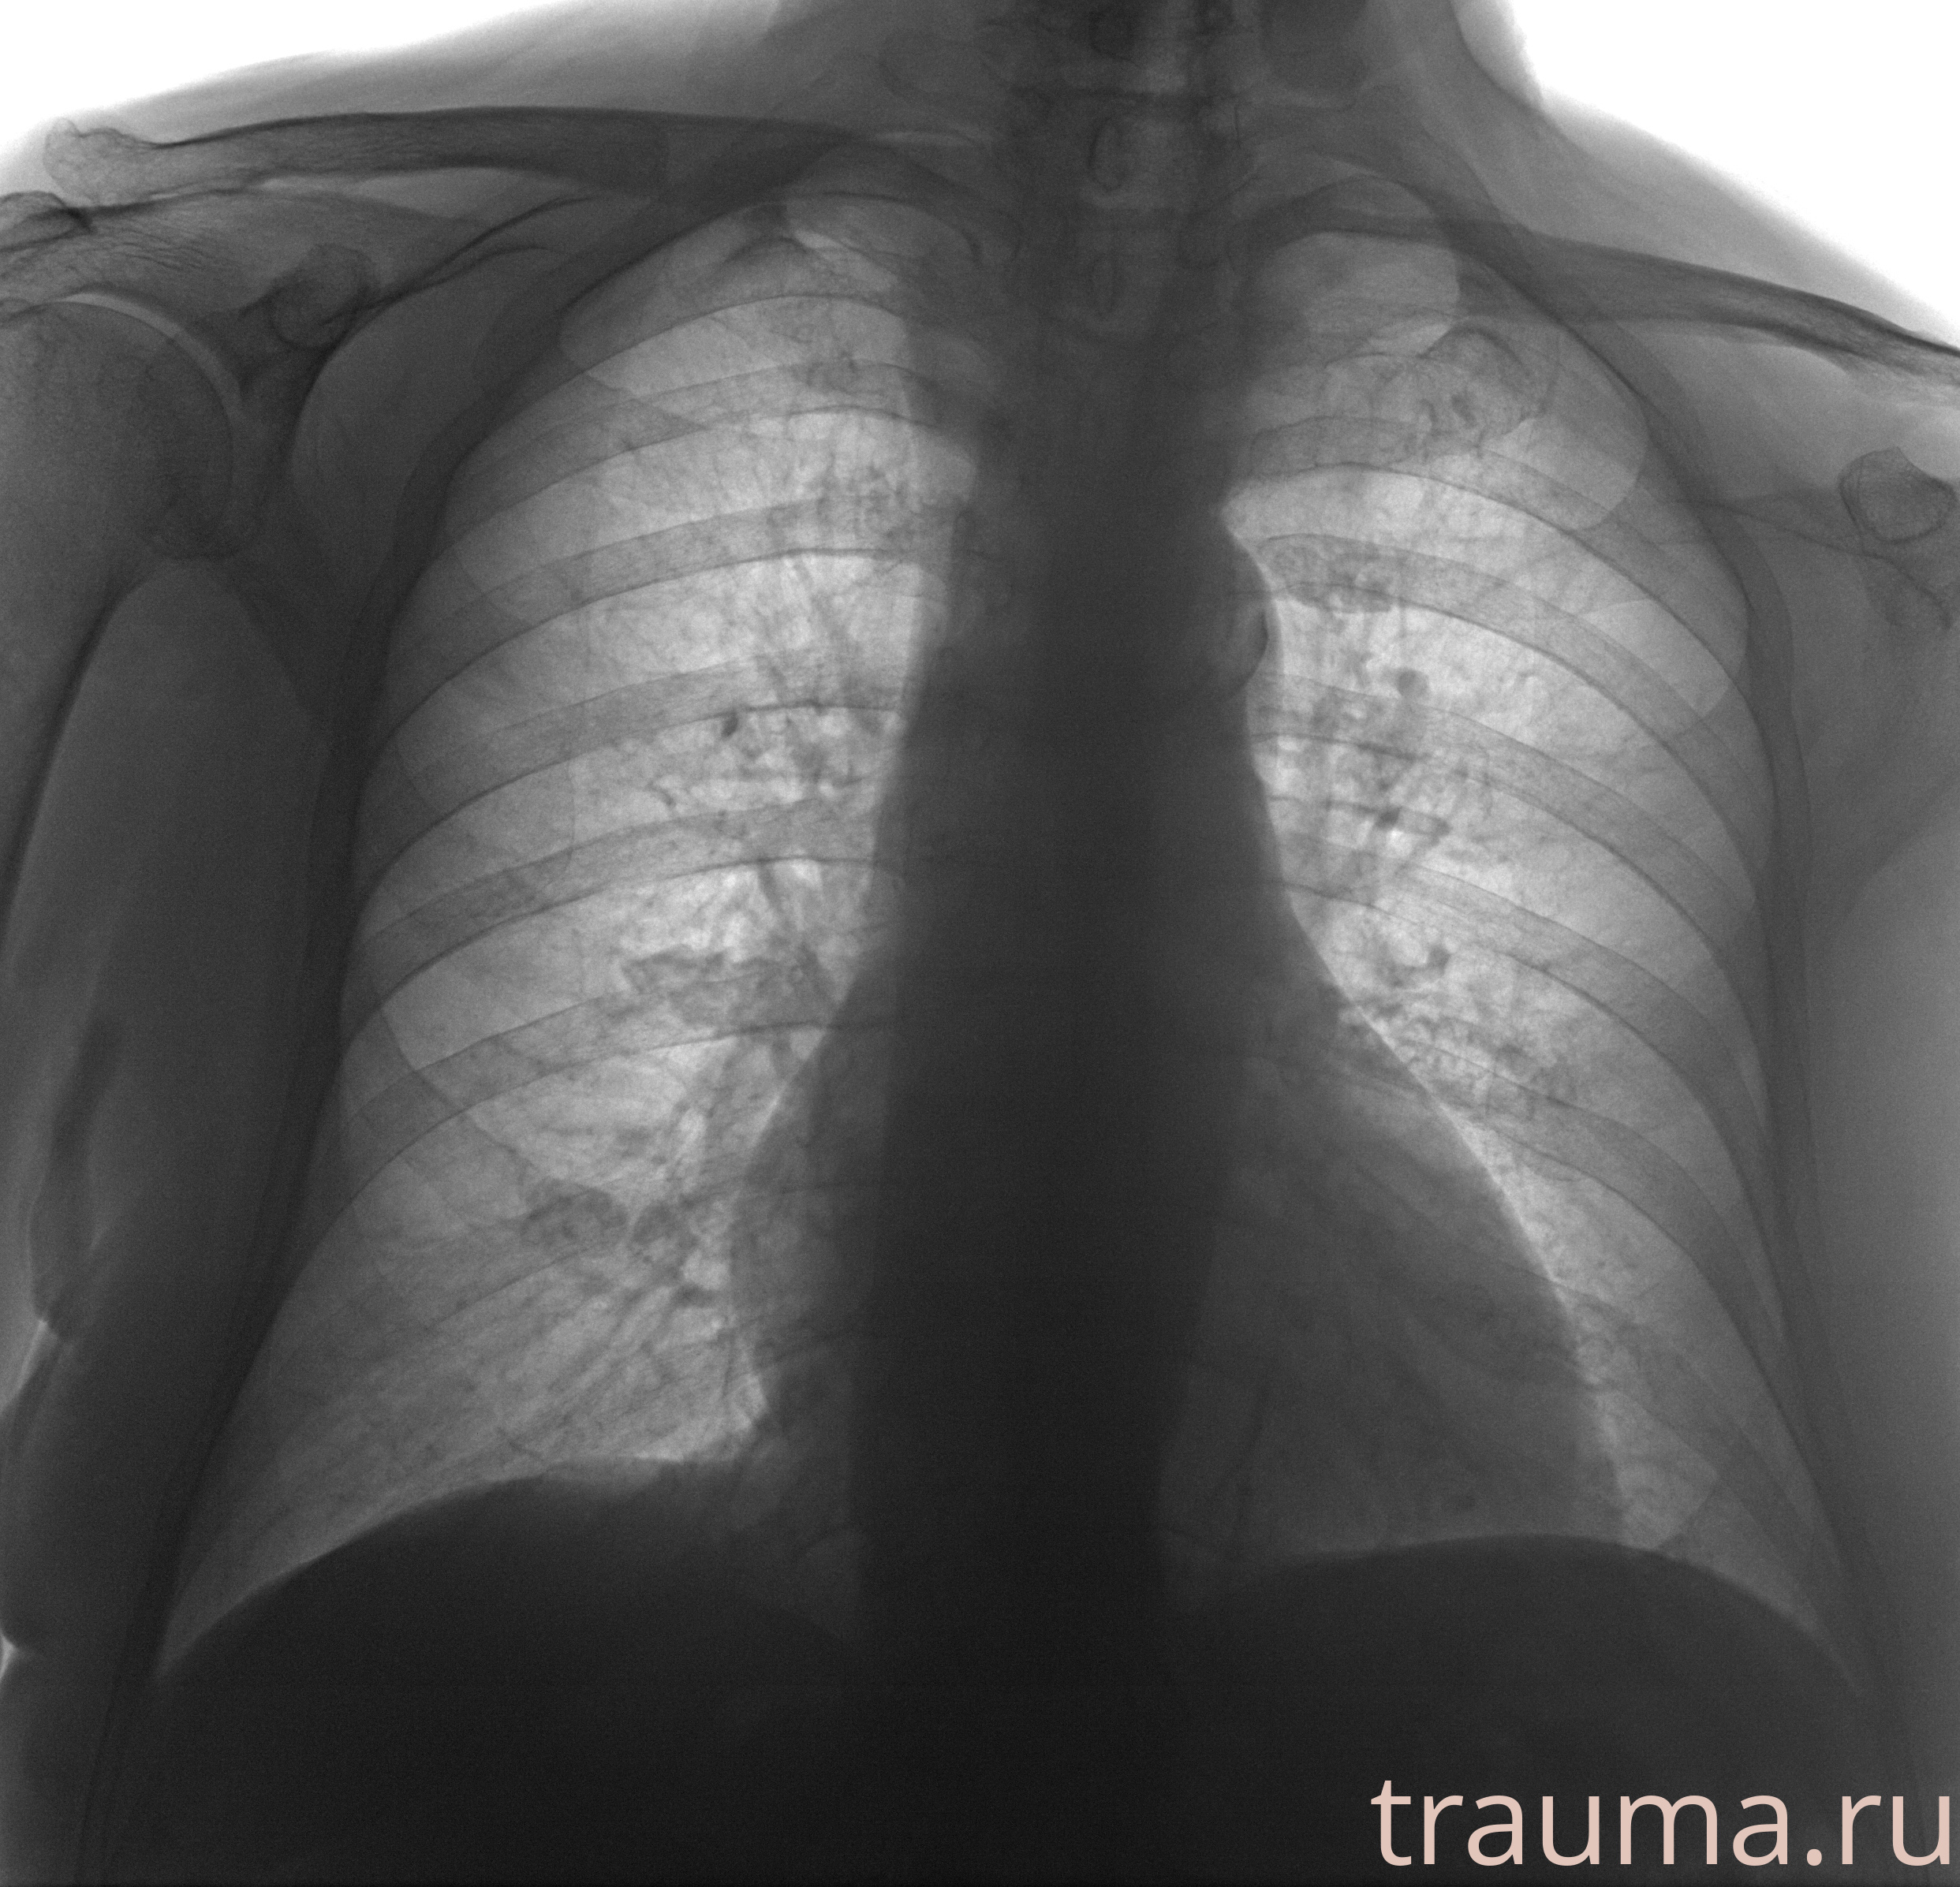

Рентгенограммы

Рентген на дому: по вашему адресу приезжает врач-рентгенолог, травматолог-ортопед с мобильным рентгеновским аппаратом, проводит диагностику травмы или заболевания, делает необходимые рентгенограммы, дает рекомендации по дальнейшему лечению. Получить качественные снимки в домашних условиях возможно благодаря уникальной методике, разработанной МосРентген Центром для института  Склифосовского

при переломе шейки бедра и пневмонии от компании МосРентген Центр - партнера Института имени Склифосовского